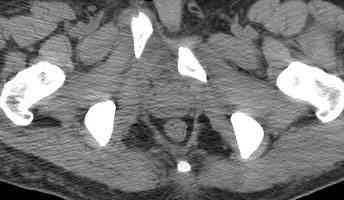

18.12. - отдельное спасибо еще раз А.В.Рункову- больного оперировали (А.В.Рунков) - произведен остеосинтез аппаратом - фиксация за крылья, два стержня в лонные кости и репозиция (почти полная) снимки будут чуть позже.

Дренировали отслойки на бедрах с их санацией. В правой ягодичной области сформировалась зона некроза. Больной "подвешен" за аппарат.